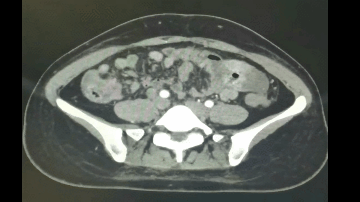

◈ 2022年7月15日,行腹部CT检查提示:盆腔见较大不规则形混杂密度影,与双侧附件及邻近肠管、右侧髂血管分界不清,最大层面约12.4cm×8.8cm,病变上下径约14.9cm,三期CT值约为28Hu、27Hu、31Hu,其内密度不均,可见片状高密度影及钙化密度影,病变周围似见稍高密度包膜影。左上腹部小肠旁另见一相同性质肿块,约4.9cm×3.2cm,边缘强化,与局部肠管分界不清。腹腔内见较多液体密度影。网膜略增厚。

◈ 检查诊断:1、盆腔占位病变,对比2022-04-30片体积稍减小、强化减低。2、腹腔积液,对比前片积液量明显增加;网膜略增厚,请结合临床。3、左上腹部小肠占位性病变,请注意复查。

◈ 考虑肿瘤进展(PD),并且左上腹部小肠占位,考虑转移,腹水量增大。

2022年7月15日 腹部CT